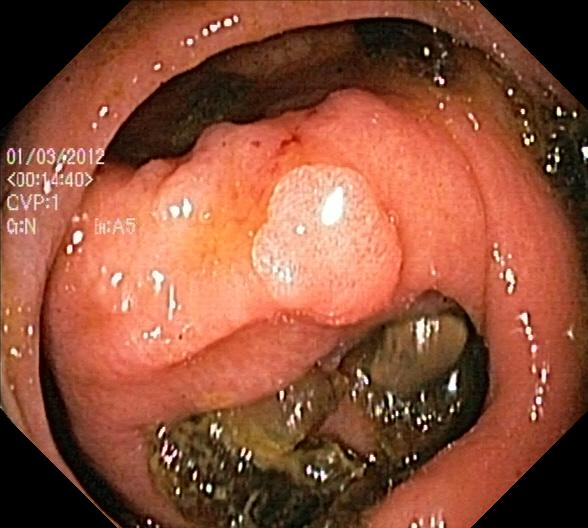

Figure 1: Polyp visual aspects have a wide variety in terms of shape and color. Four different polyps sampled from the different databases considered in this work: (a) Kvasir-Seg [19], (b) CVC-ClinicDB [5], (c) CVC-ColonDB [4], (d) ETIS [29].

The large bowel within the human gastrointestinal tract can be affected by different diseases, among which, Colorectal Cancer (CRC) is particularly concerning. CRC represents the second most common cancer type in women and third most common for men [15]. Gastro-intestinal polyps are known precursors of this type of cancer [34], being present in almost half of the patients over 50 undergoing screening colonoscopies [31]. This kind of lesions show a wide range of shapes and visual appearances, as shown in Fig. 1, turning its identification and segmentation into a challenging problem.